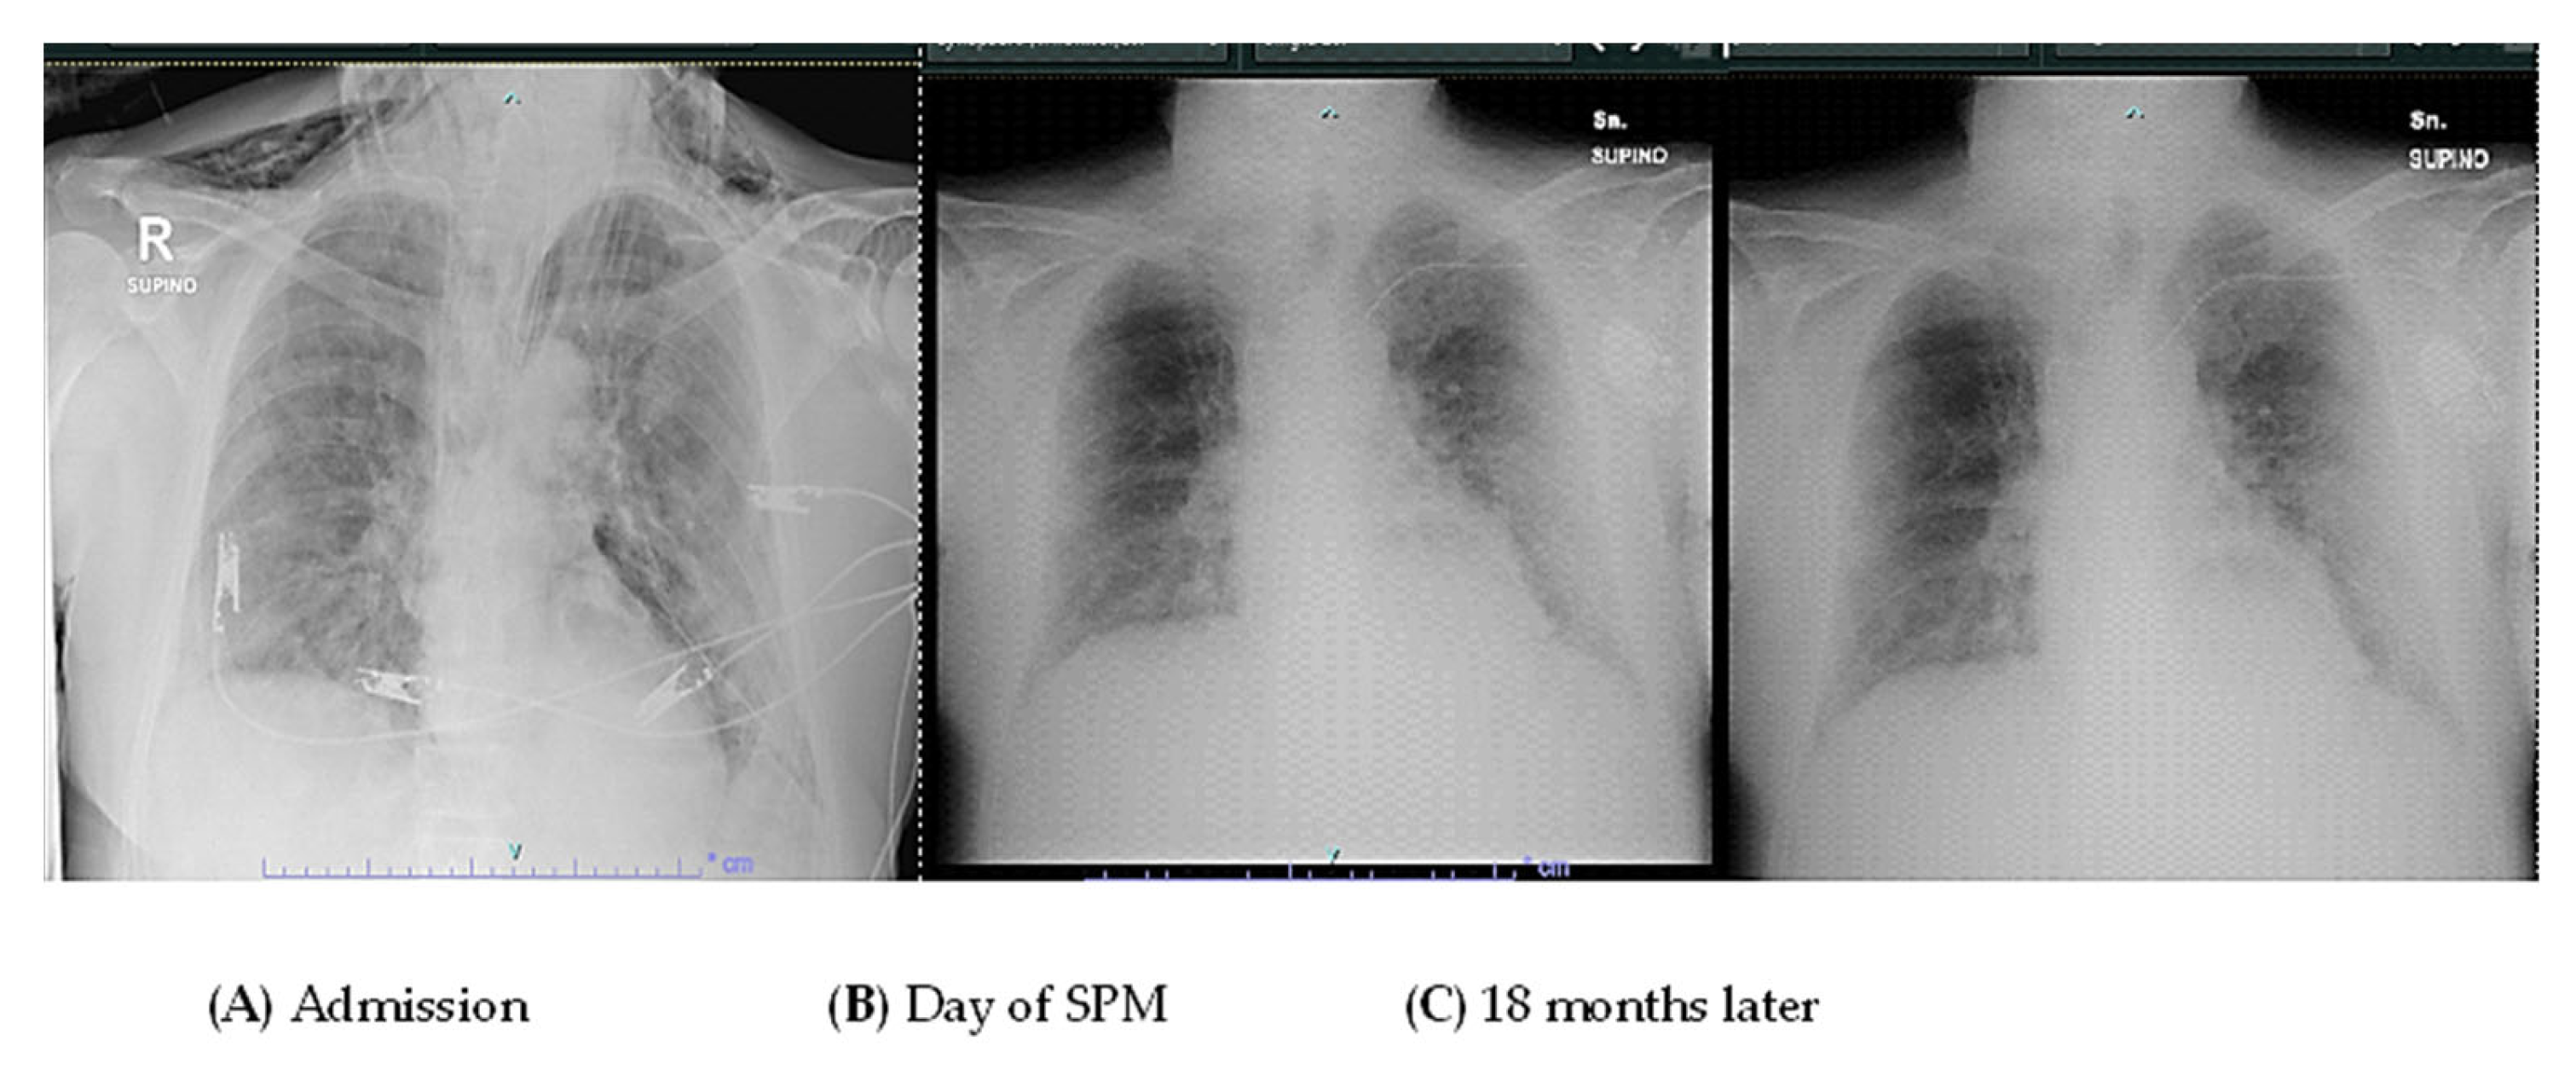

2. Case Presentation